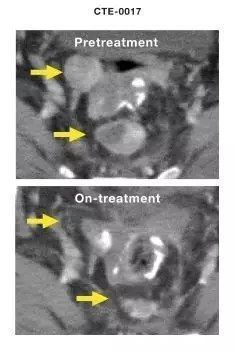

文章插图

短短几周治疗后,患者病情就得到了明显的控制 图源:《科学》杂志子刊

事实结果也证明了研究者预想,所有输入了细胞并且有了响应的患者,体内的T细胞数量不但上升了,而且他们的两年生存率达到了百分之百,而没有产生反应的患者,生存率只有25%。这就充分表明,只要患者的免疫力能够被充分激活,那么杀灭癌细胞的可能性就会大大增加,甚至于能够将癌细胞全部剿灭。